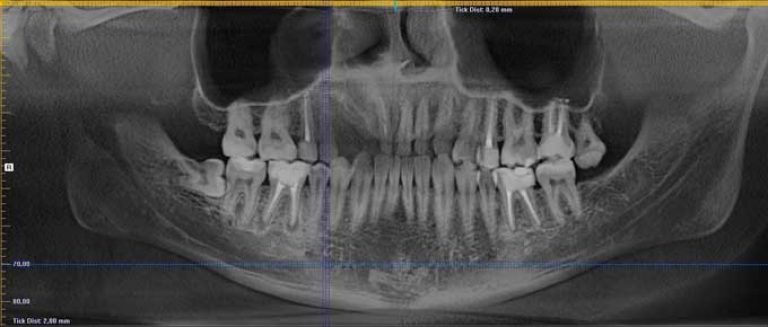

Правильный диагноз сможет поставить только стоматолог на основании сделанного рентгена. На снимке можно увидеть небольшой затемненный участок около корня зуба.

В больнице так же можно сделать радиовизиографию. Эта разновидность рентгеновского исследования с меньшим облучением. Результаты оценивают не на снимке, на экране монитора. По этой причине такое обследования часто называют цифровым.

Гранулему лучше распознать на первой стадии. Часто ее выявляют при лечении других стоматологических заболеваний. Кроме этого, доктора обращают внимание на ненормальную припухлость десны, которая обладает сильной болезненностью. Так же в область внимания врачей попадает выпирание кости около верхушки зуба.